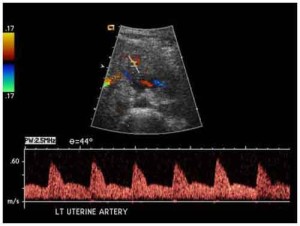

Trovato un legame tra basse dosi di vitamina D e esiti avversi della gravidanza. Lo studio della University of Calgary, Canada, e’ stato pubblicato sulla rivista British Medical Journal. preeclampsiaGli scienziati hanno scoperto un link fra l’insufficienza di vitamina D e alcune patologie come il diabete gestazionale e la pre-eclampsia, rischi di infezioni, restrizioni alla crescita del feto e le nascite di neonati sottopeso. Gli studiosi hanno analizzato dati provenienti da 31 studi compiuti fra il 1980 e il 2013 che hanno coinvolto fra 95 e 1100 partecipanti. Le donne incinta con un livello di vitamina D 5-OH basso avevano maggiori probabilita’ di sviluppare diabete gestazionale (0,49 per cento in piu’) e maggiori probabilita’ (0,79 per cento) di sviluppare pre-eclampsia. Mentre c’era una maggiore probabilita’ di dare alla luce bambini che pesavano poco, non c’era nessun significativo rischio di avere una minore lunghezza o circonferenza della testa del bimbo alla nascita.